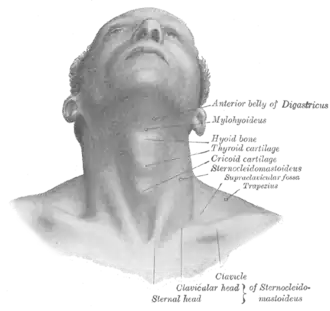

Front view of neck (supraclavicular fossa labeled at center right) | |